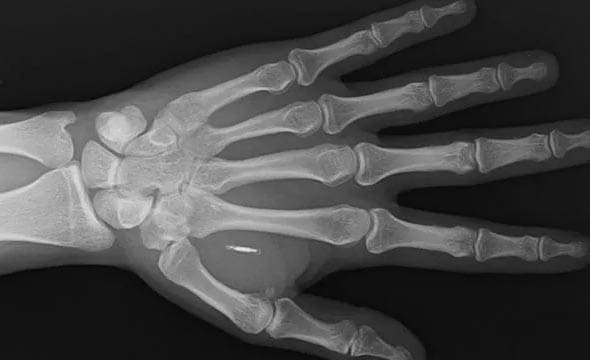

O holandês Patrick Paumen, de 37 anos, não precisa de dinheiro, cartão ou celular para pagar suas compras. O homem simplesmente coloca a mão esquerda perto do leitor e o pagamento é realizado, pois, em 2019, ele injetou um microchip de pagamento sob a pele.

O chip de Walletmor, que pesa menos de um grama e é pouco maior que um grão de arroz, é composto por um minúsculo microchip e uma antena envolta em um biopolímero, um material de origem natural, semelhante ao plástico. Paprota diz que o chip é totalmente seguro, tem aprovação regulatória e funciona imediatamente após ser implantado. Também não requer bateria ou outra fonte. A empresa diz que já vendeu mais de 500 chips.